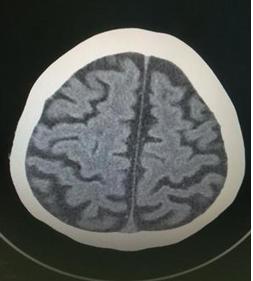

腦積水的病理改變?yōu)槟X室系統(tǒng)逐漸打大第腦室向下方隆起壓迫垂體及 視神經(jīng)交叉部,透明隔可穿破, 腦實(shí)質(zhì)變薄以額葉處最明顯,甚至穿破側(cè)腦室與蛛網(wǎng)膜下腔相通。胼胝體、錐體束、基底節(jié)、四疊體、脈絡(luò)叢及腦干等處均可因長期受壓而萎縮。白質(zhì)脫髓鞘變神經(jīng)軸受壓變形,膠質(zhì)增生及神經(jīng)細(xì)胞退行性變等。

正常情況下,腦脊液的分泌和吸收處于動態(tài)平衡狀態(tài)。但在病理情況下顱內(nèi)腦脊液過多積存于腦室系統(tǒng)或蛛網(wǎng)膜下腔內(nèi)。腦積水臨床上分為梗阻性腦積水和交通性腦積水兩大類。

阻性腦積水見于腦脊液通路受阻,在受阻以上腦室系統(tǒng)擴(kuò)大而無蛛網(wǎng)膜下腔的擴(kuò)張。多見于先天性畸形如中腦導(dǎo)水管畸形是嬰兒腦積水的主要原因,出生時常有頭顱偏大而后是頭顱呈進(jìn)行性異常增大頭身不成比例,智力發(fā)育低下,甚至有痙攣性癱瘓。其次是腫瘤直接堵塞或壓迫腦室系統(tǒng)的通道導(dǎo)致腦積水。交通性腦積水多為后天病變引起,如腦膜炎、蛛網(wǎng)膜下腔出血阻塞蛛網(wǎng)膜粒引起腦脊液吸收功能障礙使腦室系統(tǒng)和蛛網(wǎng)膜下腔擴(kuò)張。